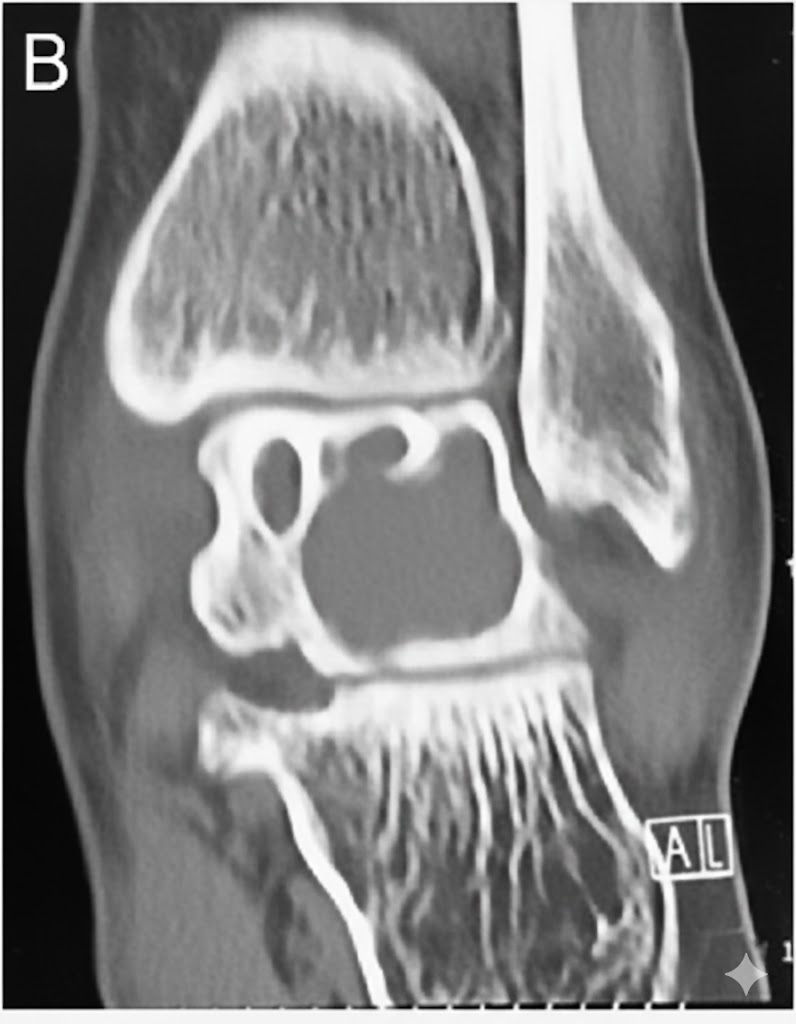

Tomografía Computarizada (TC)

Indicada si la Rx es dudosa, para planificación quirúrgica o para evaluar la cortical y posibles comunicaciones articulares.

- Confirma el borde esclerótico y la ausencia de matriz mineralizada.

- Densidad líquida (0-20 UH) en el interior.

- Puede demostrar un fino trayecto de comunicación con la articulación (presente en <30% de los casos).

- Valora con precisión la integridad de la cortical y el riesgo de fractura.